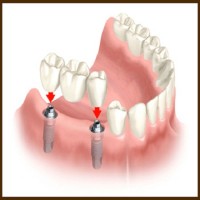

Las Vegas Dental Implants cxz4skjtlz

Версия 1 от 20.08.2011

Las Vegas Dental Implants

Implants In Las Vegas rjzht2mzkjs

Версия 1 от 19.08.2011

Implants In Las Vegas